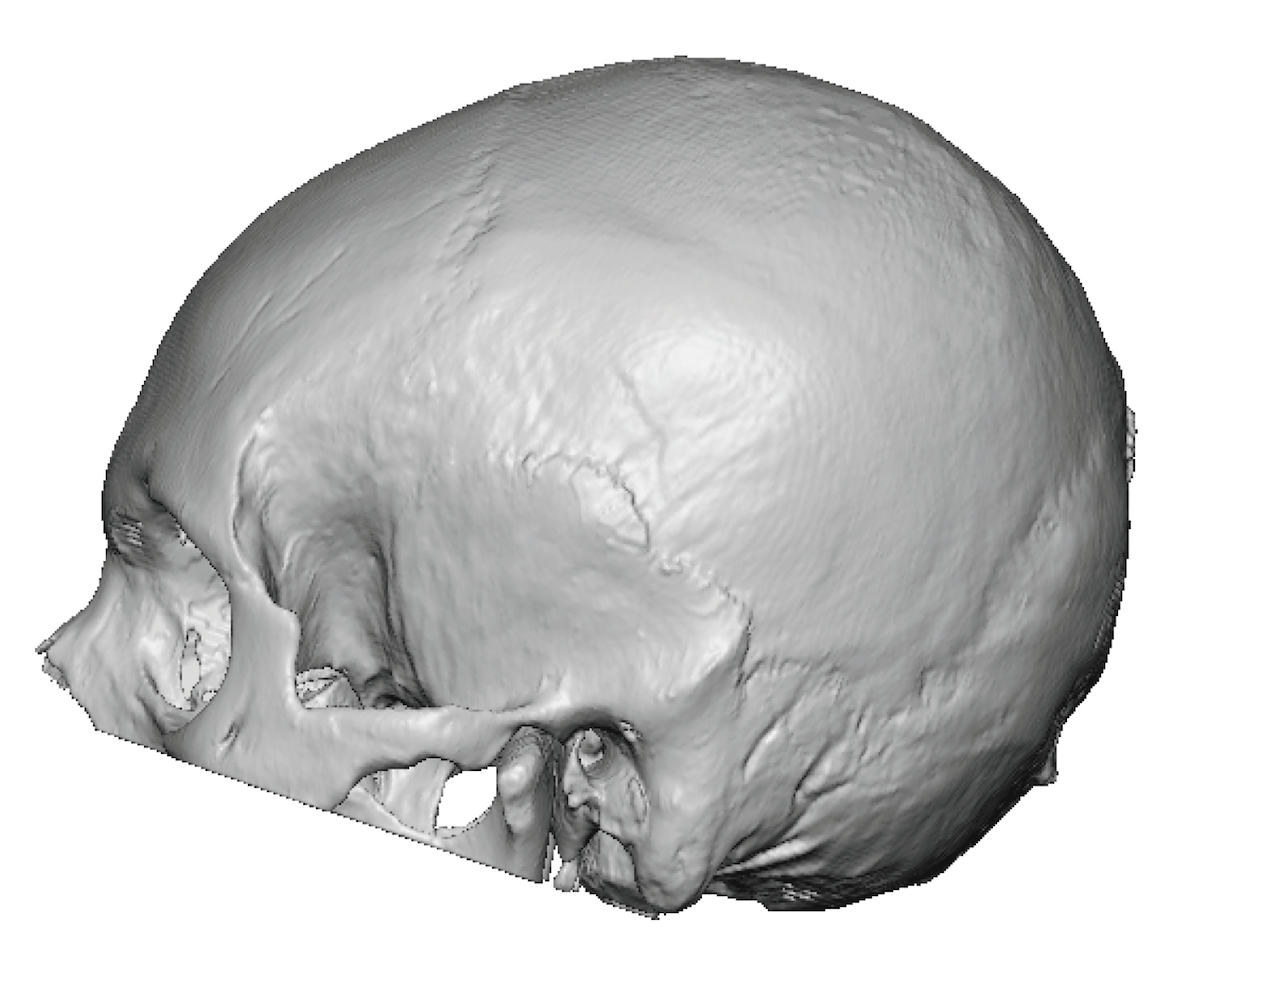

Severe narrowing skull deformity from prior sagittal craniosynostosis repair as an adult.

Complete replacement of entire skull by a custom implant with temporal fat injections.

Severe narrowing skull deformity from prior sagittal craniosynostosis repair as an adult.

Complete replacement of entire skull by a custom implant with temporal fat injections.